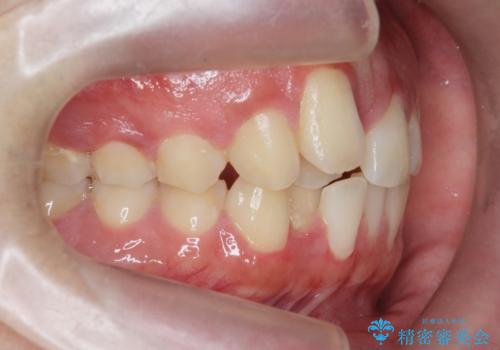

正中過剰埋伏歯で生じた前歯の審美障害 矯正治療での改善

- 前歯の見た目に悩まれて来院されました。

当初他院では、抜歯を行いセラミックブリッジを提案されていましたが、他の方法はないかと総合歯科治療を行う当院へと相談来院されました。

「時間がかかっても良いので、できれば歯を抜かずに矯正治療で治したい。」という強い希望があったので、矯正治療で歯並び・審美性の改善を計画します。

見た目、噛み合わせが大きく改善し、大変喜んでいただくことができました。